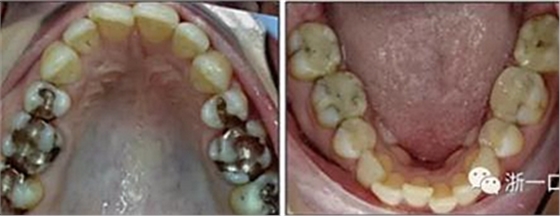

患者曾行正畸治療,現(xiàn)覺笑容不美觀前來就診。患者正面觀及側(cè)貌示下頜發(fā)育不足,偏高角,唇閉合不全。上下頜中線齊。覆合、覆蓋4毫米。磨牙關(guān)系及尖牙關(guān)系II類。上頜擁擠度4mm,下頜擁擠度6mm。4顆第一前磨牙在第一次正畸治療時已拔除。上下牙弓呈尖圓型,牙弓狹窄。

頭影測量分析,SNA角84°,ANB角6°,高角型,詳見下表。